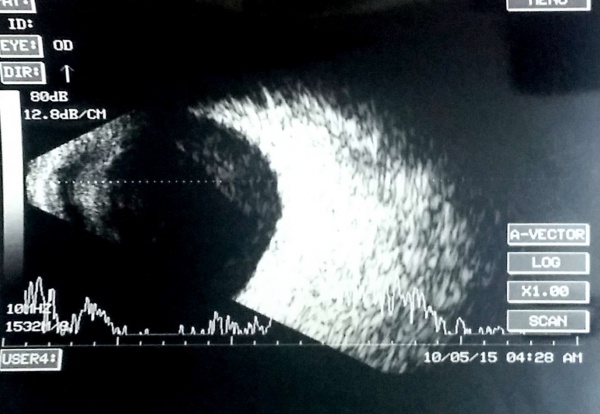

Ultrasonographic features of choroidal detachment (CD)

A CD is denoted by a round mound which is limited by the strong uveoscleral attachments (scleral spur, vortex veins, and optic nerve). It has limited mobility and an A scan passing perpendicularly through a CD shows 'M' (double peak) shape. The shape is typically of a smooth dome, usually not attached to the optic disc. The fluid in the suprachoroidal space may be anechoic (serous CD) or have mild to moderate amplitude point echoes (hemorrhagic CD). When CDs touch each other they are called kissing choroidals, and such cases may be more prone to permanent adhesion and may guide the timing of surgery in suprachoroidal hemorrhage. USG also notes the clot lysis in suprachoroidal hemorrhages and guides timing of surgery, and the location of the suprachoroidal hemorrhage guides the area of drainage.